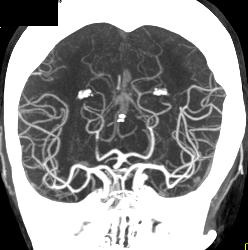

CTA With Dual Energy and Bone Removal